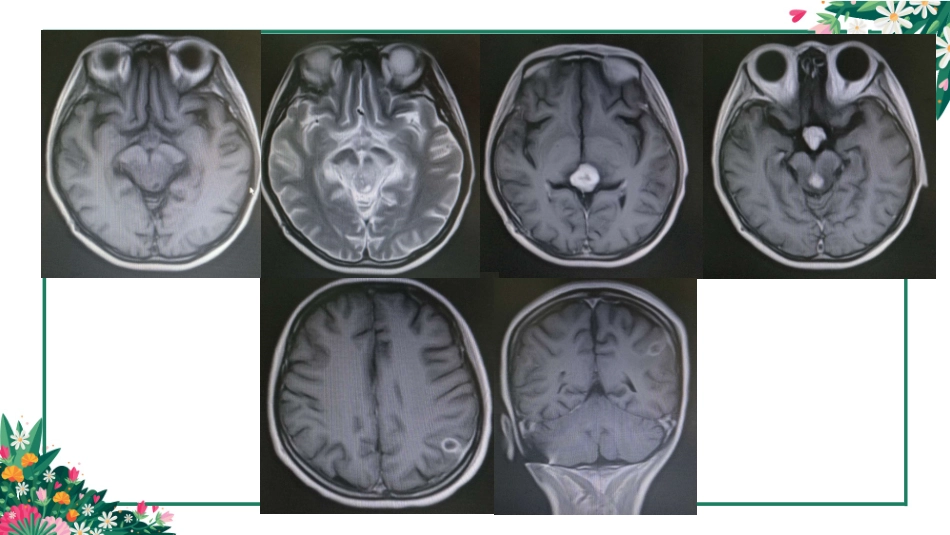

颅内生殖细胞瘤及其鉴别(germcelltumor,GCT)贵州医科大学2016级简要病史患者女,24岁,2年前无明显诱因出现闭经,后视物模糊,有重影,无头晕、头晕、口角歪斜、言语含糊等,现患者大小便失禁、感头痛,视物模糊症状加重,就诊于我院,行头颅MRI。如图所示。概述•生殖细胞肿瘤是发生于生殖腺或生殖腺外的肿瘤,由原始生殖细胞或多能胚细胞转型而形成;原始的生殖腺发育成熟为卵巢或睾丸,并分别下降至盆腔、阴囊,在此过程中,原始生殖腺也可发生异位移行,因此生殖细胞肿瘤除了可以原发于卵巢和睾丸外,还可以发生在性腺外(extragonadal),且多位于中线附近。头颅颈部纵隔腹膜后骶尾椎病理分型WHO的病理分类将GCTs分为6个亚型:生殖细胞瘤、畸胎瘤、内胚窦瘤(又名卵黄囊瘤)、绒毛膜上皮癌(简称绒癌)、胚胎癌、混合性生殖细胞瘤(混合性生殖细胞瘤为其他组织学成分混合而成)。除生殖细胞瘤(germinomas)以外的肿瘤总称为非生殖细胞瘤性生殖细胞肿瘤(nongerminomatousgermcelltumors,NGGCTs)。生殖细胞瘤约占GCTs的50~70%。流行病学•亚洲的发生率明显高于欧美国家•高峰年龄:10-12岁(90%<20岁)•颅内好发部位为松果体及鞍上区,比例约为2:1。约5%~10%的病人肿瘤在这两个部位同时出现,这种情况绝大多数都属于生殖细胞瘤。•性别特征•松果体区男性多见(70%的男性病人)•鞍上区女性多见(75%的女性病人)•基底节、丘脑和大脑半球几乎为男性解剖视束垂体海绵窦颈内动脉大脑中动脉动眼神经滑车神经视神经上颌神经基底节豆状核杏仁核屏状核尾状核临床表现松果体区中脑导水管受压颅内高压头痛、恶心呕吐、意识障碍、癫痫发作可表现为性早熟鞍区下视丘—垂体系统尿崩症最常见导致视力和视野障碍可表现为发育迟缓基底节区肢体活动障碍松果体区生殖细胞瘤影像诊断与鉴别01松果体区起源于松果体腺02起源于松果体腺周围生殖细胞瘤畸胎瘤松果体细胞瘤松果体母细胞瘤中间分化型胶质瘤脑膜瘤转移瘤非肿瘤性病变:囊肿、脂肪瘤胚胎生殖细胞分化松果体主质细胞分化松果体区生殖细胞瘤•50%松果体肿瘤•软组织肿块–CT高密度–“增强明显,V”字征•“Engulf”松果体,中心钙化•囊变,出血少见CT平扫为松果体区圆形、类圆形或浅分叶实性病灶,呈等密度或稍高密度,常有松果体的钙化斑块包裹其中或挤向边缘。三脑室后部受压变形,若肿瘤向前沿三脑室两侧壁生长使三脑室后部呈V字形,尖端指向肿瘤,瘤体呈蝴蝶状,是松果体区生殖细胞瘤较为特征的表现。生殖细胞瘤MRI为等或稍长T1长T2信号,增强扫描时病灶明显均匀强化。少数病灶内可有出血和囊变。肿瘤可有多发及沿脑脊液种植于蛛网膜下腔、室管膜下及软脑膜,需增强扫描明确。•15%松果体肿瘤•小儿和青年人多见,男>女•可分为囊性和实质性,囊性多为良性,实质性者多为恶性•因有牙齿、骨、脂肪等组织,CT上为高低不等密度,MRI图像上畸胎瘤在各个序列上表现为不均质松果体区畸胎瘤畸胎瘤‘松果体主质细胞肿瘤特点•发病年龄较生殖细胞瘤大(20-40岁)•多见于青年女性,生殖细胞瘤多见于青少年男性•“”呈爆炸钙化灶,生殖细胞瘤常推压松果体钙化移位•很少发生坏死、囊变及出血•“”松果体瘤不具有生殖细胞瘤侵犯三脑室后部形成的蝴蝶征•鞍上池、基底节区及脑实质内有肿瘤病灶时考虑生殖细胞瘤•患者性征发育迟缓或不发育CT呈类圆形等密度或稍高密度影,MRI为等或稍长T1稍长T2信号,边界清楚,周围无水肿,可见钙化,无出血、囊变及坏死。增强扫描肿瘤轻到中度均匀强化,少数呈不均匀强化。松果体细胞瘤为起源于松果体实质的良性肿瘤,占松果体区肿瘤的15%以下,多发生于青年女性,平均年龄34岁。WHO分级为Ⅱ级。松果体细胞瘤松果体母细胞瘤松果体母细胞瘤WHO分级为Ⅳ级,肿瘤较早侵犯第三脑室并沿脑脊液途径播散转移,形成脊髓和脑膜种植。松果体母细胞瘤常较大,形体不规则,呈浸润性生长,无包膜,与邻近组织分界不清,CT平扫成等密度或稍高密度或等低混杂密度,肿瘤内出血、坏死囊变常见,钙化罕见。MRI为混杂T1长T2信号,DWI为高信号。增强扫描肿瘤明显不均匀强化。中等分化松果体实质肿瘤中间分化的松果体实质瘤...